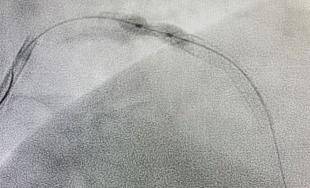

年1月9日2024,管室同舟共济CCU、导,腔内打击波球囊导管成形术(IVL)何义医师主刀为患者行经皮冠状动脉。2mm打击波球囊术膺选3.5*1,原支架膨胀不全处导管置于前降支,放打击波脉冲4个周期以4atm压力下释,m非适合性球囊扩张支架后通过3.5*15m,胀优良支架膨。超声验证经血管内,支架膨胀优良原膨胀不全处,全体、管腔获取明显IVUS见支架膨胀,术成果得意造影见手,无不适患者,病房安返。

球囊定位至LAD近中段3.5*12mm打击波,通过3.5*15mm非适合性球囊扩张支架正在4atm压力下开释打击波脉冲4个周期后,胀优良支架膨。

个月近一,心绞痛症状患者再发,队充判袂论经手术团,IVUS辅导术中适宜采用,质、订定手术政策以精准评估病变性,管内打击波管理支架膨胀不全题目最终决策以Shockwave血,环形斑块松解、震断将支架膨胀不全处,张球囊扩张再行后扩,膨胀全体形态使支架到达。